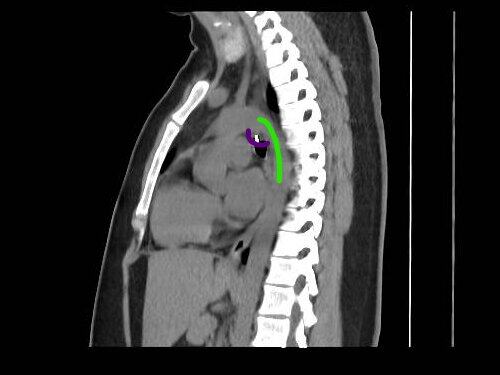

Mesec dana sam uporno kašljala: Lekari nisu mogli da veruju šta su mi pronašli u plućima, 0,5 milimetara od aorte

profimedia-1089210767.jpg

4 / 4

Jam Press / Jam Press / Profimedia